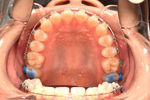

叢生(そうせい)・がたがた・永久歯萌出スペース不足

主訴:不正咬合の恐れ・2┴2の萌出スペース不足

年齢:8y8m

診断:叢生

装置・期間:

第一期治療 上下顎拡大装置(クアッドヘリックス・バイヘリックス)+上顎マルチブラケット装置 3年7カ月間(9y0m~2y7m)

第二期治療 上下顎マルチブラケット装置 1年間(12y11m~13y11m)

保定 上下顎保定装置 2年間以上

治療費:第一期治療 矯正基本料400,000円+処置料3,000~6,000円×27回(別途消費税)

第二期治療 矯正基本料400,000円+処置料3,000~6,000円×12回(別途消費税)

保定装置料 50,000円(別途消費税)